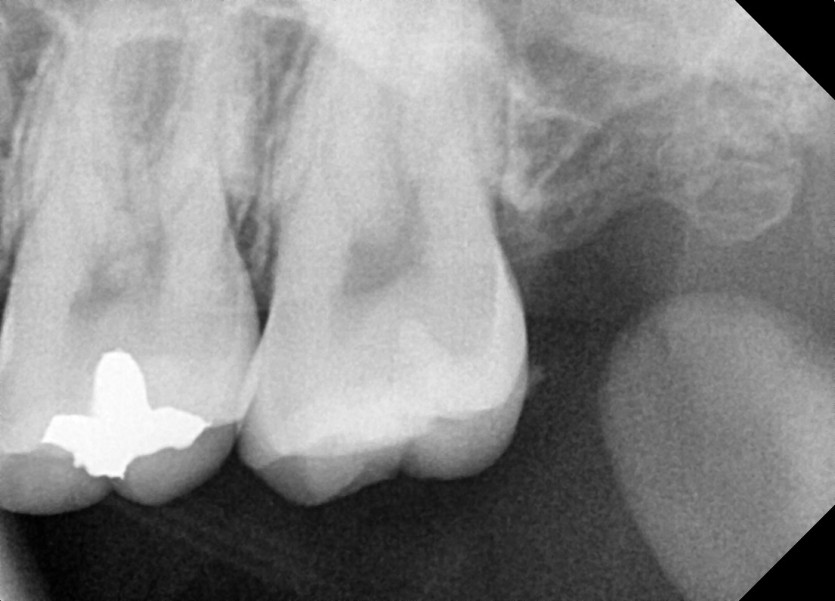

#28 사랑니 발치

구강 외과 전문의가 당일 발치했습니다.